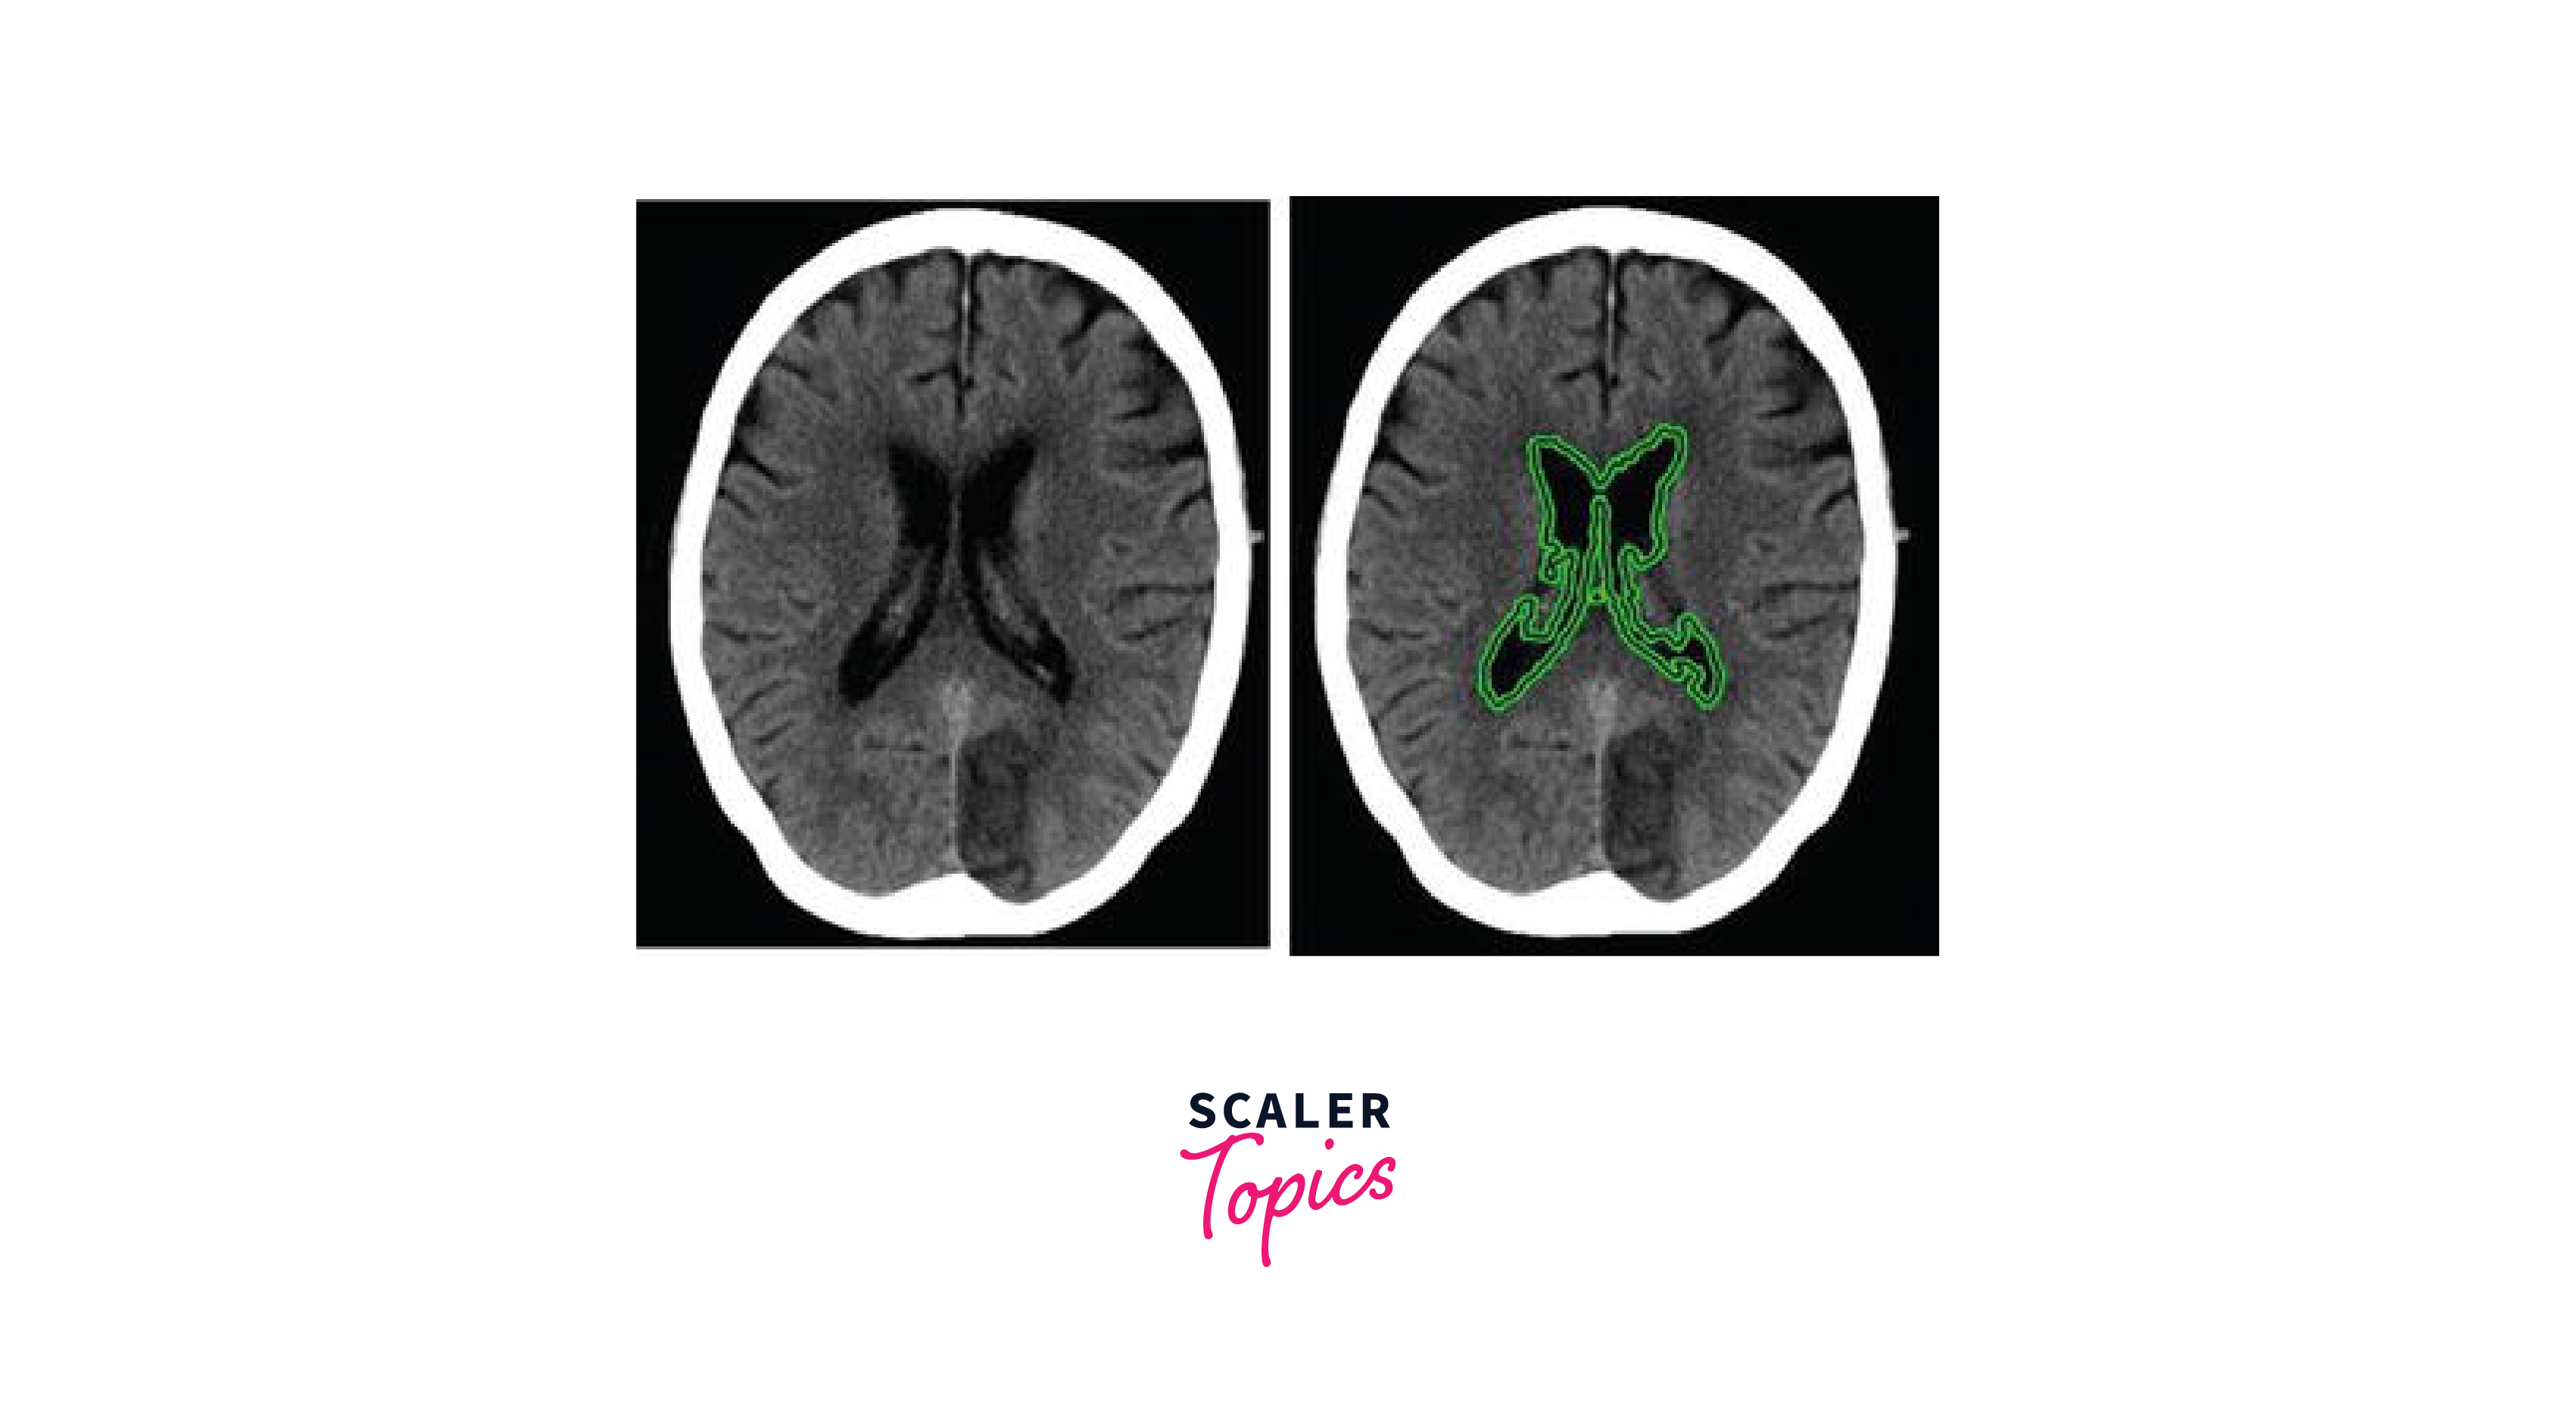

Image Segmentation of Medical Images

Medical image segmentation is a crucial step in many medical imaging applications, such as tumour detection, image-guided surgery, and radiation therapy planning. In this section, we will discuss how to perform the segmentation of medical images using OpenCV in Python. Specifically, we will use thresholding and morphological operations to segment the image and extract the region of interest.

Next, we read in the medical image that we want to segment. In this example, we will use an MRI brain image.

Finally, we find contours on the segmented image. Contours are the boundaries of objects in an image. In this case, we are interested in finding the contours of the tumours in the medical image.

After finding the contours, we can draw them on the original medical image using the cv2.drawContours function. We can also calculate the area and perimeter of each tumour by using the cv2.contourArea and cv2.arcLength functions.